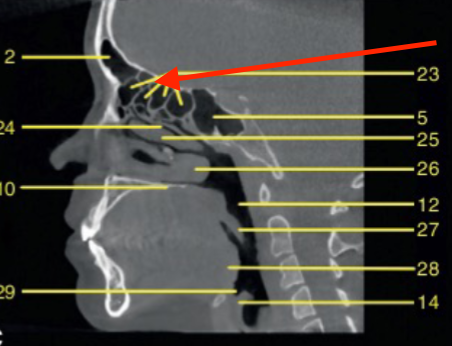

nasopharynx

identify the region indicated

oropharynx

identify 5

soft palate

identify the structure

tongue

palatine tonsils

epiglottis

C1

lateral pterygoid plate

what structure is the arrow pointing to

pterygopalatine fossa

hyoid

sella turcica